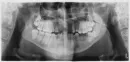

Можно ли по квоте провести операцию по остеотомии?

У меня отсутствует 4 передних верхних зуба, еще по одному с каждой стороны молочные зубы. Если их удалить, будет 6 отсутствующих зубов.

В 3-х клиниках мне сказали, что ничем помочь в протезировании не могут, нужна операция остеотомия обеих челюстей. В имплантации отказали, в съемных протезах тоже. Коренные зубы не вылезли с детства, даже снизу ещё имеются молочные зубы.

Сколько это будет стоить примерно? Если можно сделать квоту, как ее оформить? Что делать?

В первую очередь рекомендуется провести ортодонтическую коррекцию, после чего заняться протезированием с подсадкой костной ткани.